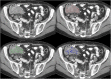

Methods: Image texture analysis is an approach of quantifying heterogeneity that may not be appreciated by the naked eye. Different methods can be applied including statistical-, model-, and transform-based methods.

Results: Early evidence suggests that texture analysis has the potential to augment diagnosis and characterization as well as improve tumor staging and therapy response assessment in oncological practice.

Conclusion: This review provides an overview of the application of texture analysis with different imaging modalities, CT, MRI, and PET, to date and describes the technical challenges that have limited its widespread clinical implementation so far. With further efforts to refine its application, image texture analysis has the potential to develop into a valuable clinical tool for oncologic imaging. TEACHING POINTS : • Tumor spatial heterogeneity is an important prognostic factor. • Image texture analysis is an approach of quantifying heterogeneity. • Different methods can be applied, including statistical-, model-, and transform-based methods. • Texture analysis could improve the diagnosis, tumor staging, and therapy response assessment.